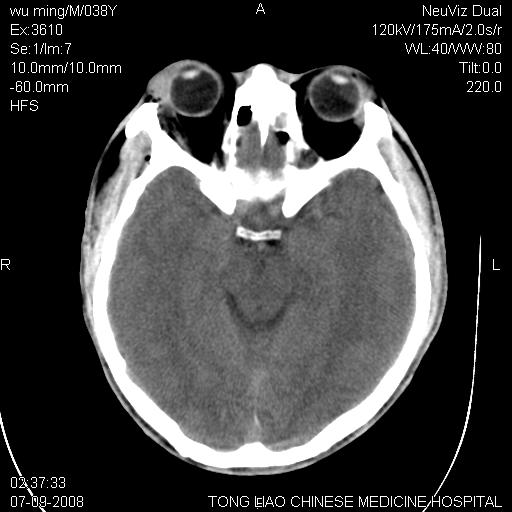

考虑:面骨、颅底骨多发骨折,颅内高压(脑肿胀)。

面骨、颅底骨多发骨折,右侧硬膜下小血肿,弥漫轴索损伤,死亡原因可能是多种因素致。

不除外轴索损伤

颅底骨折,窦腔内积血。考虑死亡原因为脑水肿压迫脑干或因大量失血死亡。

考虑:面骨、颅底骨多发骨折。从五楼摔下还伤着头了,不死才怪;估计有弥漫性轴索损伤。